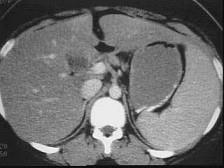

下列图像最可能的诊断是 ( )A.脂肪肝B.肝囊肿C.肝血管瘤D.原发性肝癌E.肝炎肝硬化

问题 下列图像最可能的诊断是 ( )

选项 A.脂肪肝 B.肝囊肿 C.肝血管瘤 D.原发性肝癌 E.肝炎肝硬化

答案 A